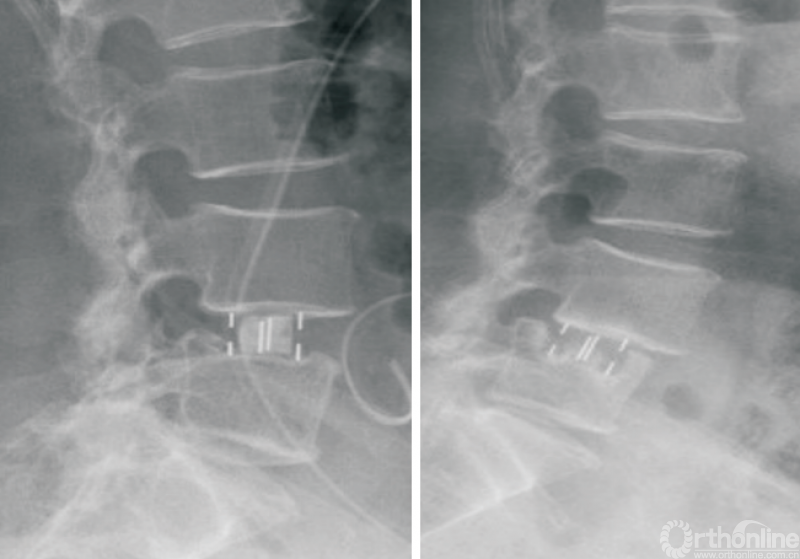

OLIF联合后路固定(图1)是治疗脊柱滑脱等失稳性疾病的经典方式[5-9],在有效减压、恢复脊柱稳定性的同时,可以避免后方肌肉、韧带等结构的损伤。相关的研究对比OLIF以及经椎间孔入路腰椎椎间融合术(transforaminal lumbar interbody fusion,TLIF)手术治疗退行性腰椎滑脱,结果表明,两者在改善术后疼痛等方面没有明显差异,且具有住院时间短、出血量少、术后腰痛较轻等特点[10-12]。

图1 经典的OLIF

CHUNG等[13]的研究表明,相较于前入路腰椎椎间融合术(anterior lumbar interbody fusion,ALIF)手术,OLIF在恢复椎间隙高度及节段前凸方面更加具有优势;葛腾辉等[14]研究证实,OLIF联合后路固定治疗退行性腰椎滑脱能进一步减少腰椎退行性滑脱患者的滑移率,并增加手术节段前凸角度。

俞仲翔等[6]研究证实,对于邻椎病的治疗,OLIF可以取得与后路腰椎椎间融合术(posterior lumbar interbody fusion,PLIF)等经典手术方式同样的效果,且能够缩短手术时间,减少并发症的发生。王志强等[15]研究证实,OLIF联合单侧或双侧的椎弓根螺钉固定均可有效治疗腰椎退行性疾病。CHO等[16]研究表明,对于存在矢状位失衡的退行性脊柱侧弯患者,OLIF联合后路螺钉治疗比传统的PLIF更加有效。因此,经典的OLIF技术可以应用于脊柱侧弯、脊柱滑脱、腰椎椎管狭窄等众多腰椎退行性疾病的诊疗。